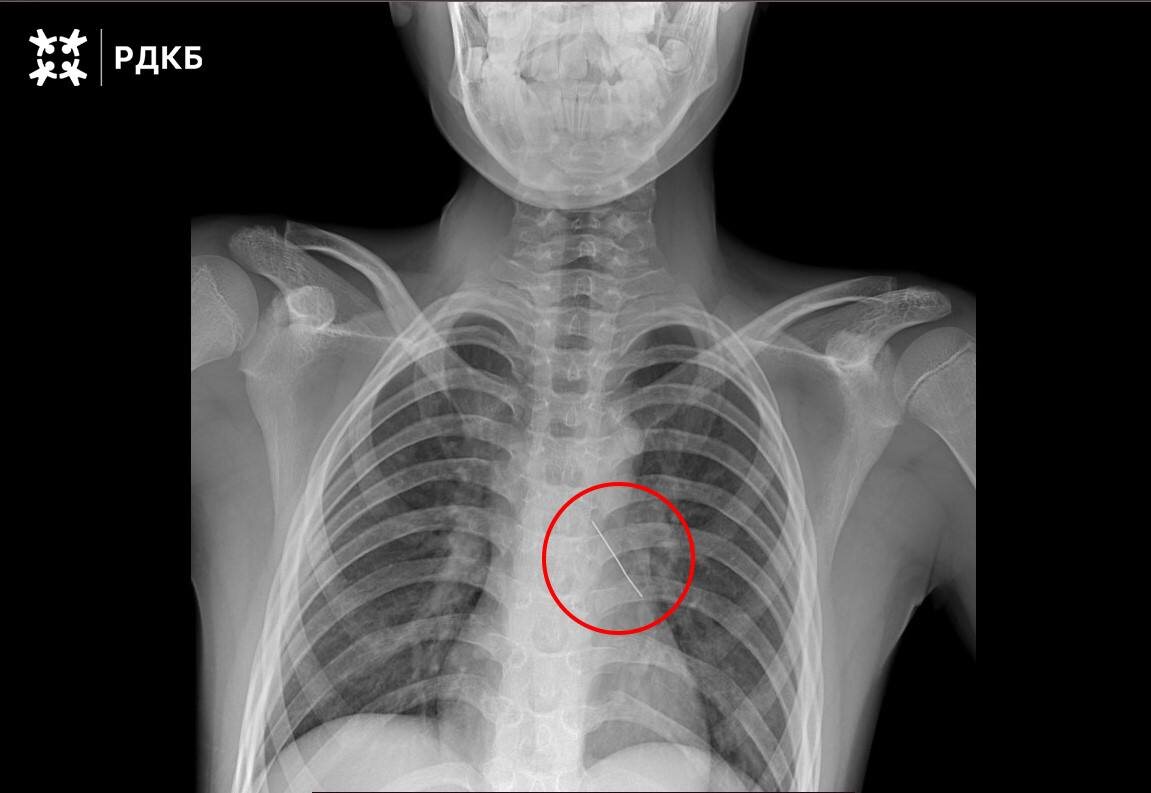

Московские хирурги совершили настоящее чудо, спася 11-летнего мальчика, который случайно вдохнул булавку. Подростка экстренно доставили бортом санавиации из Калининградской области в Российскую детскую клиническую больницу. 🚨

Операция прошла успешно: врачи аккуратно извлекли инородный предмет с помощью оптических щипцов. Уже через три дня мальчика выписали домой, и теперь он чувствует себя отлично. 💪